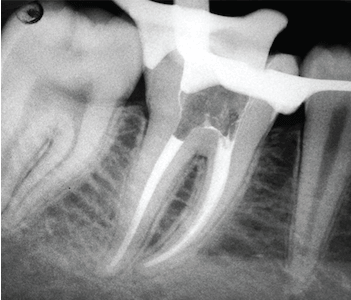

El endodoncista realiza una perforación en la corona del diente para poder llegar a la pulpa, extraerla y proceder a la limpieza del conducto. A continuación, se rellena y se sella cada uno de los conductos radiculares y la cámara para matar el nervio y el suministro de sangre del diente.

Nuestros dentistas especialistas en endodoncia recomiendan realizar exámenes anuales y radiografías después del tratamiento de conducto radicular.